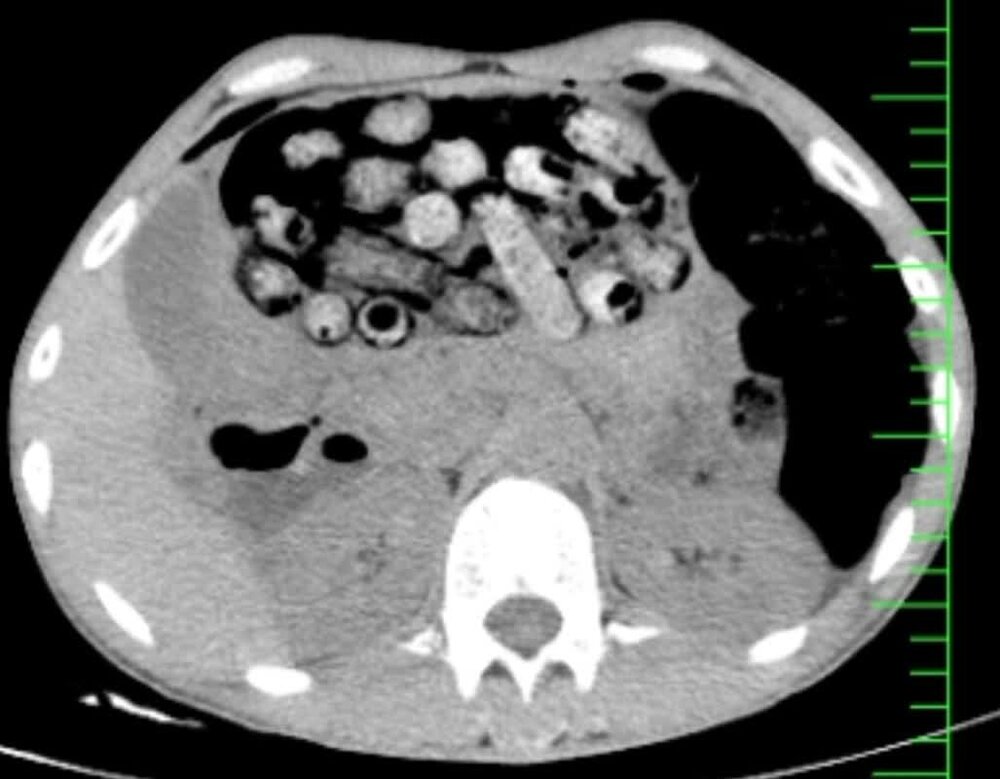

براساس اطلاعات اولیه مأمور همراه، بیمار پیش از مراجعه، اقدام به بلع تعدادی بسته محتوی مواد مخدر کرده بود. در پی انجام تصویربرداری فوری، تعداد زیادی بسته مشکوک در معده و روده کوچک و بزرگ وی مشاهده شد.

با توجه به خطر بالای پارگی احتمالی بستهها و بروز عوارض تهدیدکننده حیات، بیمار بلافاصله به اتاق عمل منتقل شد و جراحی سنگین وی از ساعت سه بامداد آغاز شد.

در این جراحی که به سرپرستی دکتر سامان شیخی، عضو هیأت علمی گروه جراحی عمومی دانشگاه علوم پزشکی البرز و با همکاری تیمهای اورژانس، تصویربرداری، بیهوشی و جراحی انجام و ۹۰ بسته از معده و روده بیمار خارج شد.